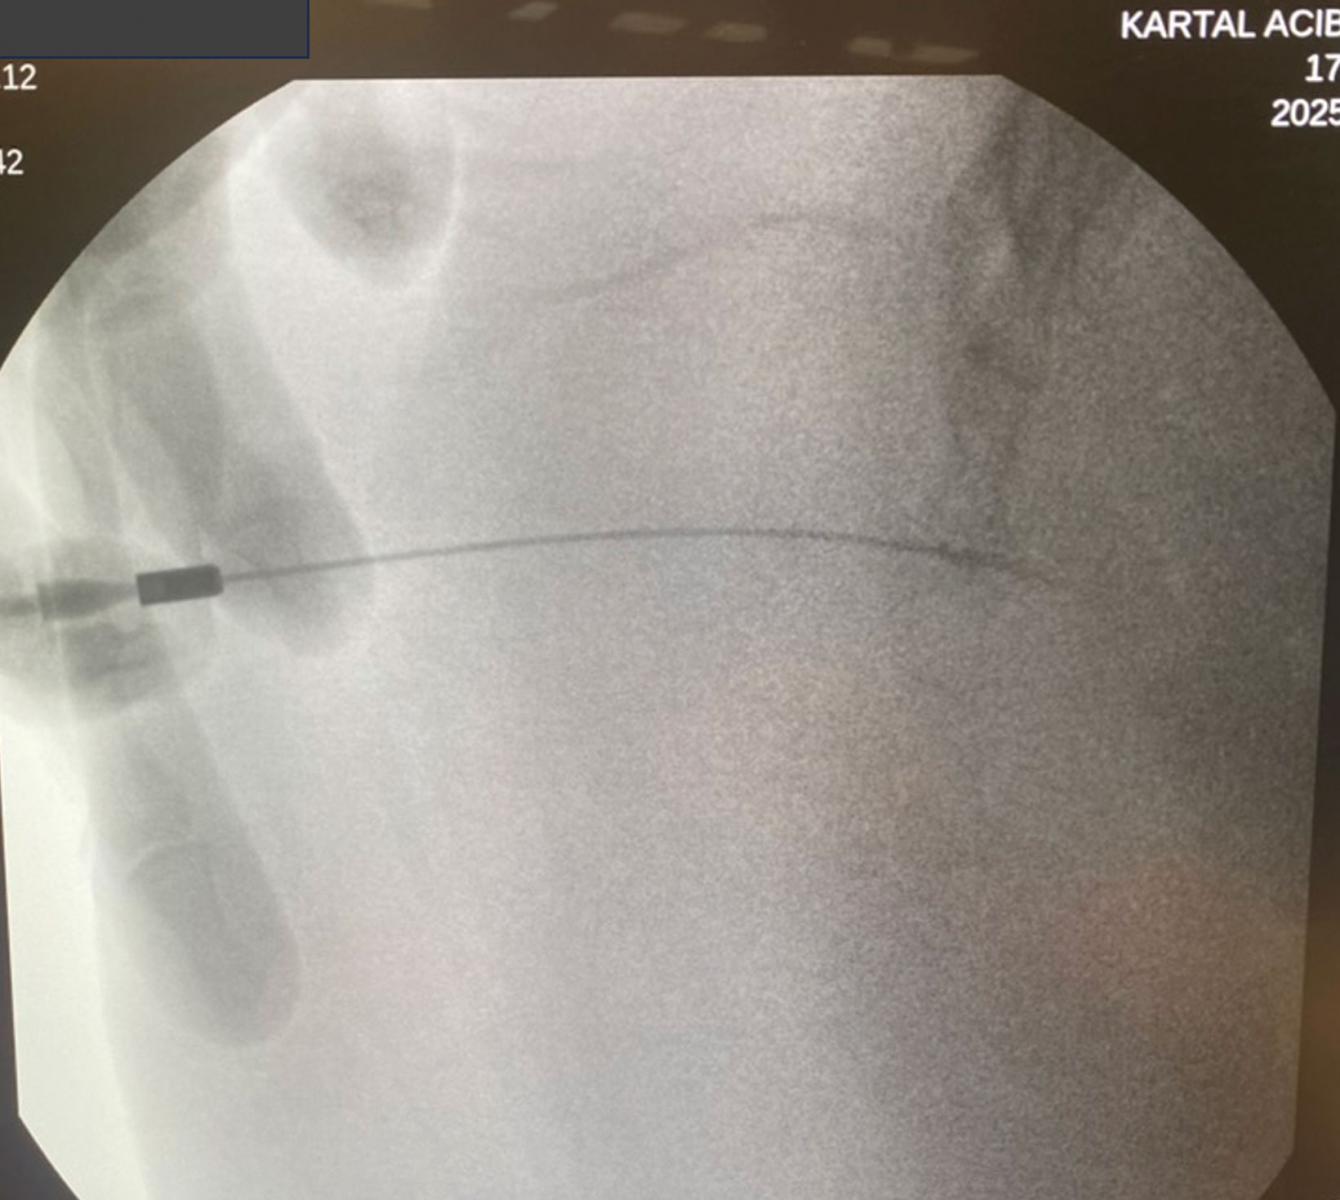

Görüntü Kılavuzluğu (Floroskopi): İşlemi röntgen (floroskopi) cihazı altında, gerçek zamanlı görüntüleme ile yapıyoruz. Bu, işlemin son derece hassas ve güvenli olmasını sağlamaktadır. İlacı tam olarak hedeflenen noktaya, çevre dokulara zarar vermeden ulaştırabiliyoruz. Amacımız "körlemesine" değil, "görerek" en doğru noktayı tedavi etmektir.

İlgili eklemden geçilerek ön alana girilir.

Kontrast verilerek gangliyon yeri doğrulanır

Steroid içerikli ilaç karışımı enjekte edilerek blokaj sağlanır.